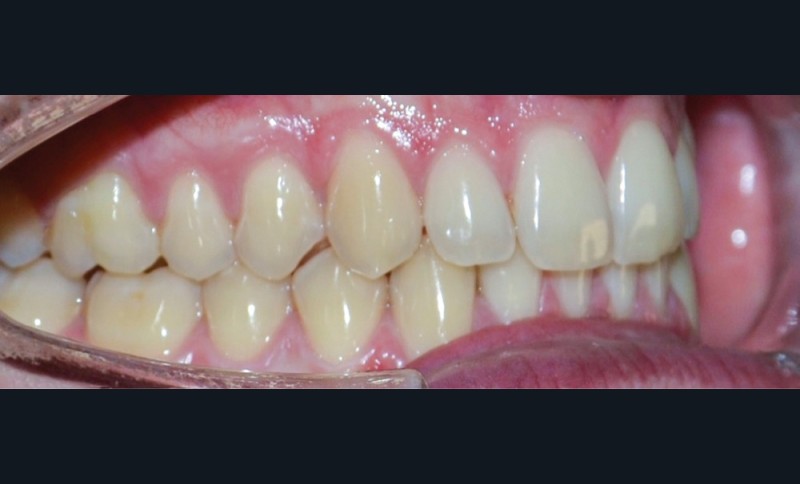

► L’entretien semi-directif met en évidence des signes d’apparition récente (un an environ), une aggravation progressive des symptômes, et la perception rapportée par le patient de moindres contacts occlusaux du côté gauche. L’examen clinique extra-oral révèle des douleurs musculaires lors de la palpation des muscles masséters, temporaux et ptérygoïdien médial gauche ainsi que des muscles sterno-cléïdo-occipito-mastoïdiens droit et gauche. Il n’y a pas de limitations d’ouverture buccale. L’examen clinique intra-oral révèle la présence d’une inocclusion dentaire gauche, qui s’étend des dents 23 à 27 (fig. 1 et 2). Il est à noter que la reprise de l’entretien ne rapporte pas d’antécédent de soins dentaires, orthodontiques et/ou prothétiques susceptibles d’engendrer une modification de l’occlusion.